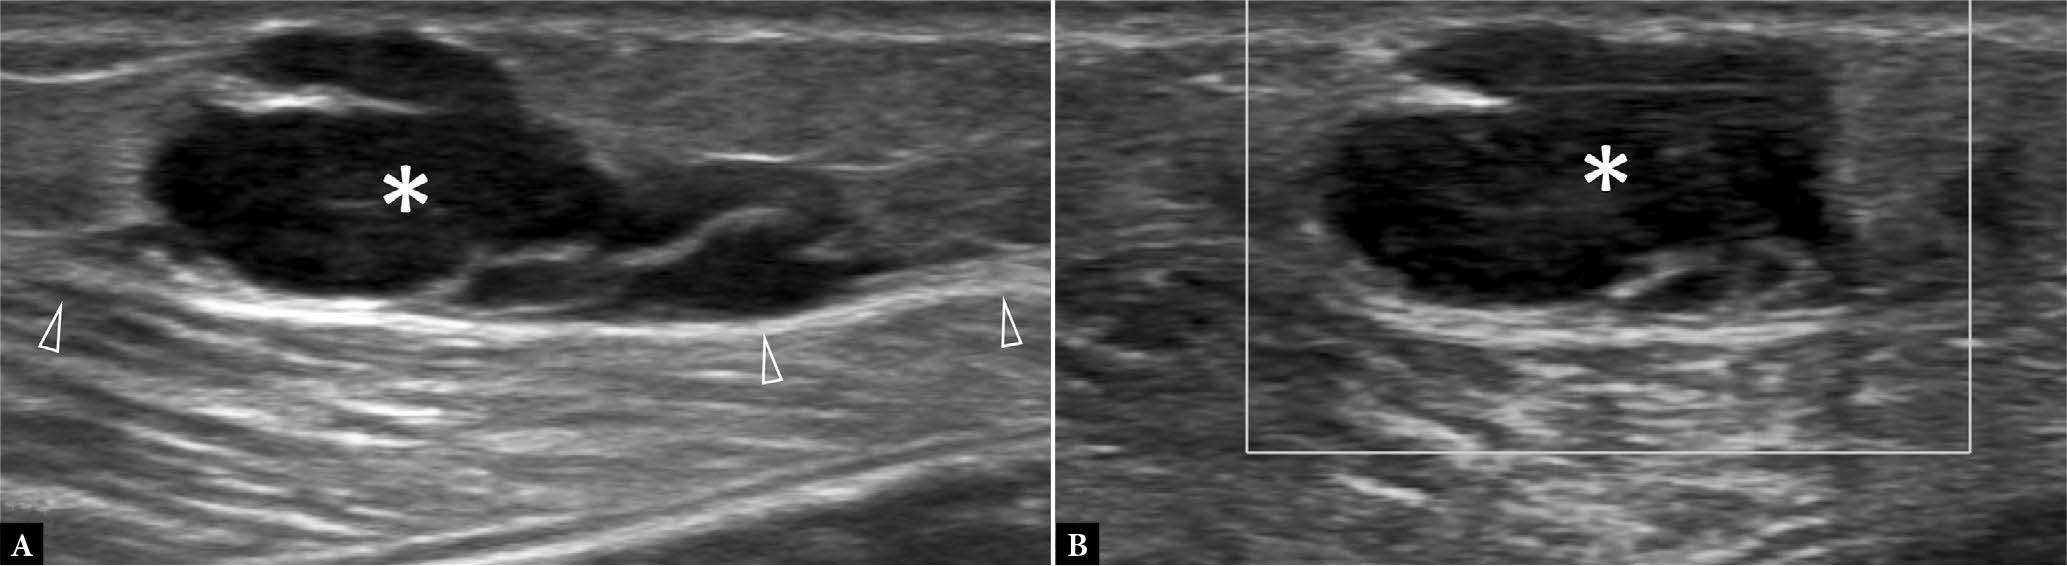

62-year-old female with slow-growing radial-sided wrist mass for two years. A. Longitudinal, B. transverse greyscale and C. longitudinal color Doppler US show a soft tissue mass (arrowheads) surrounding the 1st extensor compartment tendons (*), compatible with giant cell tumor of tendon sheath (GCTTS). Dynamic ultrasound can help to exclude intratendinous extension. GCTTS was confirmed on surgical excision

Fig. 7.